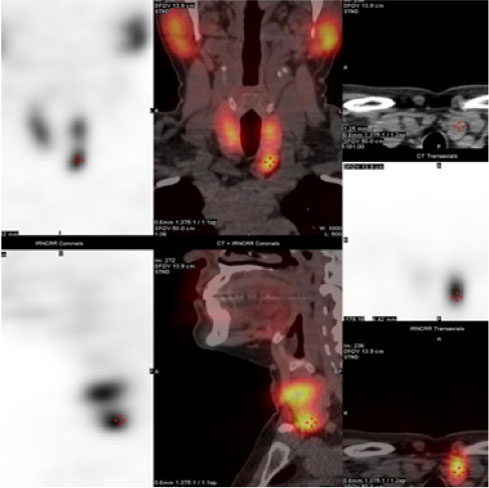

• Thyroid Uptake & Scan

• Parathyroid Scan